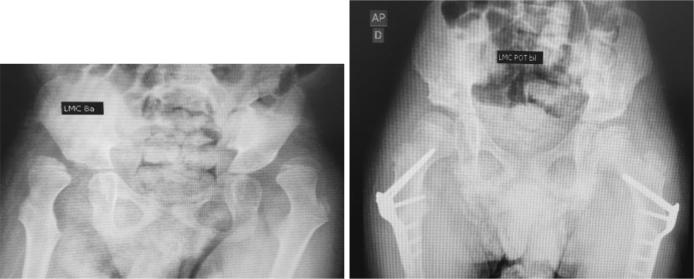

A retrospective study of 42 patients (61 hips) with cerebral palsy, gross motor functional classification system class IV or V, submitted to OVRF. The minimal follow up was 24 months. This study evaluated clinical (age at surgery, gender, Gross Motor Functional Classification System class, anatomical cerebral palsy classification, and motor pattern), pre- and post-operative radiological (neck shaft angle, acetabular index, Reimers migration index and time until bone healing) characteristics, as well as post-operative complications.

Mean pre-operative cervicodiaphyseal angle, acetabular index, and Reimers migration index were respectively 121.6°, 22.7°, and 65.4% in uncomplicated cases, and 154.7°, 20.4°, and 81.1% in complicated ones. All parameters were statistically significant difference between pre- and postoperative values ( < 0.05). The patients with postoperative complications had a greater cervicodiaphyseal angle and Reimers migration index ( < 0.0001). There were no differences in clinical characteristics, time of immobilization, or bone healing. Fourteen patients had postoperative complications (33.3%), but only six required surgical treatment.

The locked plate is a safe resource, with low complication rates and reproducible technique for OVRF in the cerebral palsy population classified as gross motor functional classification system IV and V. Greater cervicodiaphyseal angles and Reimers migration index are associated with greater chances of postoperative complications, as well as gross motor functional classification system V classification.